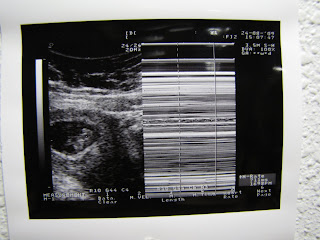

Second Ultrasound picture from the FIRST VISIT. 8 weeks+